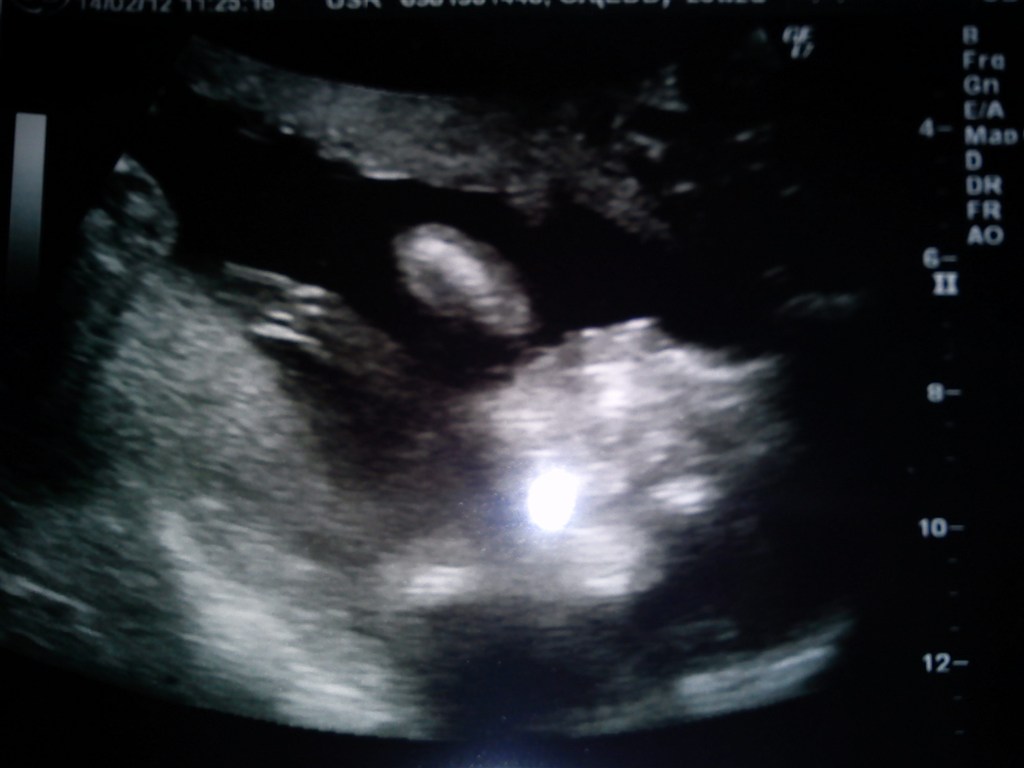

Så har mig og kæresten været til scanning idag og babyen har det perfekt og den fejler intet

Scannings damen gættede på en pige, men slet ikke med sikkerhed

Så kommer der lige et billede (ikke så godt) men man kan se næsen og armene